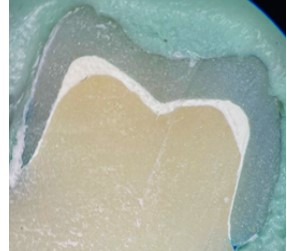

Microleakage Evaluation of PMMA Provisional Crowns Made with CAD/CAM Technique

Mohammed Al-Maqaleh, Dr., Mohammed A. Albaili (Author)

480 - 484